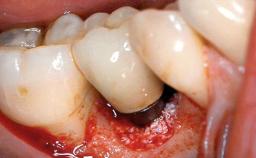

Peri-implantitis Treated with Access-Flap Surgery

A 27-year-old male was referred to the periodontist for assessment and management of implant site 41. The implant had been placed nine years previously and restored with a screw-retained single crown. The patient was a cigarette smoker in good general health. He reported he had reduced his smoking habit from 25 cigarettes per day to 15 cigarettes per day in the previous six months. On examination, there was calculus and plaque present at the lower anterior teeth and at implant site 41. Localized attachment loss was observed at teeth 32 and 42, with 2–3 mm of gingival recession. At implant site 41, there were 8–9 mm probing depths with suppuration and bleeding on probing.